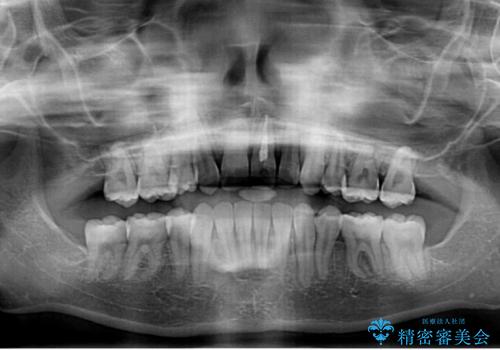

口元を積極的に引っ込めるために、上下左右の小臼歯を4本抜歯することとしました。

右上前から2番目の歯が欠損しているため、①矯正治療により欠損部にスペースを作りインプラント補綴を行って前歯を左右対称に揃える、②左右非対称となるが、欠損補綴を行わずに排列する、のいずれかとなりますが、患者様と相談の上②にて矯正治療を行うこととしました。

変則的な歯列であったため、奥歯がしっかりと咬み合うのか、前歯はしっかりと排列できるのかと不安ではありましたが、結果としてはきれいに整った歯列にて終了することができました。